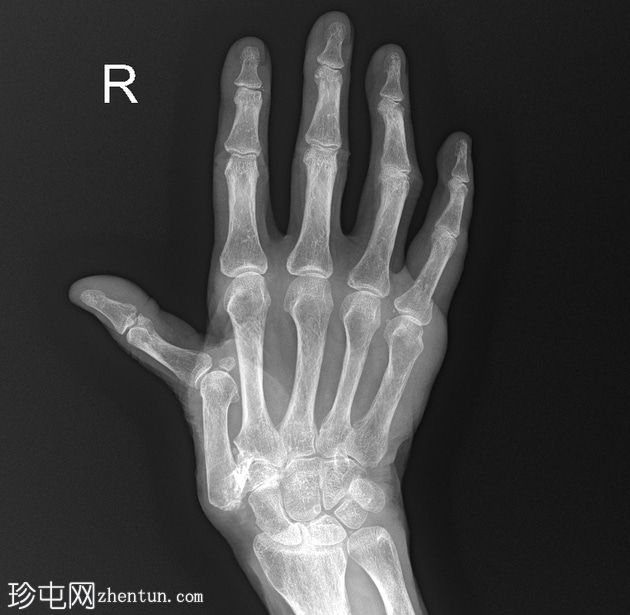

右手X线片

X线片

正位

斜位

小指近节指骨干轻微移位螺旋形骨折,周围软组织肿胀。怀疑拇指掌骨基底部和大多角骨骨折。

第一腕掌关节脱位,周围软组织肿胀。

第二至第五腕掌关节正常。桡腕关节、掌指关节和指间关节正常。尺骨茎突正常。

骨密度降低。